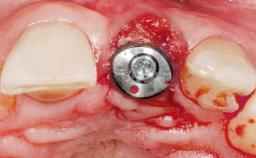

A 30-year-old female patient was referred to the office for the treatment of tooth 11. Her chief concern at the initial visit was to inquire, “Why is my tooth pink?” Upon clinical examination, it was determined that tooth 11 had a previous history of trauma and that the clinical crown had become noticeably pink in color as a result of internal resorption. This diagnosis was confirmed radiographically, indicating a large radiolucency involving the central and distal portions of the clinical crown. It was determined that restoration of this tooth was not possible, and that extraction was indicated. The presence of a mid-line diastema, which the patient wanted to reproduce, directed the treatment plan for tooth replacement utilizing a dental implant.